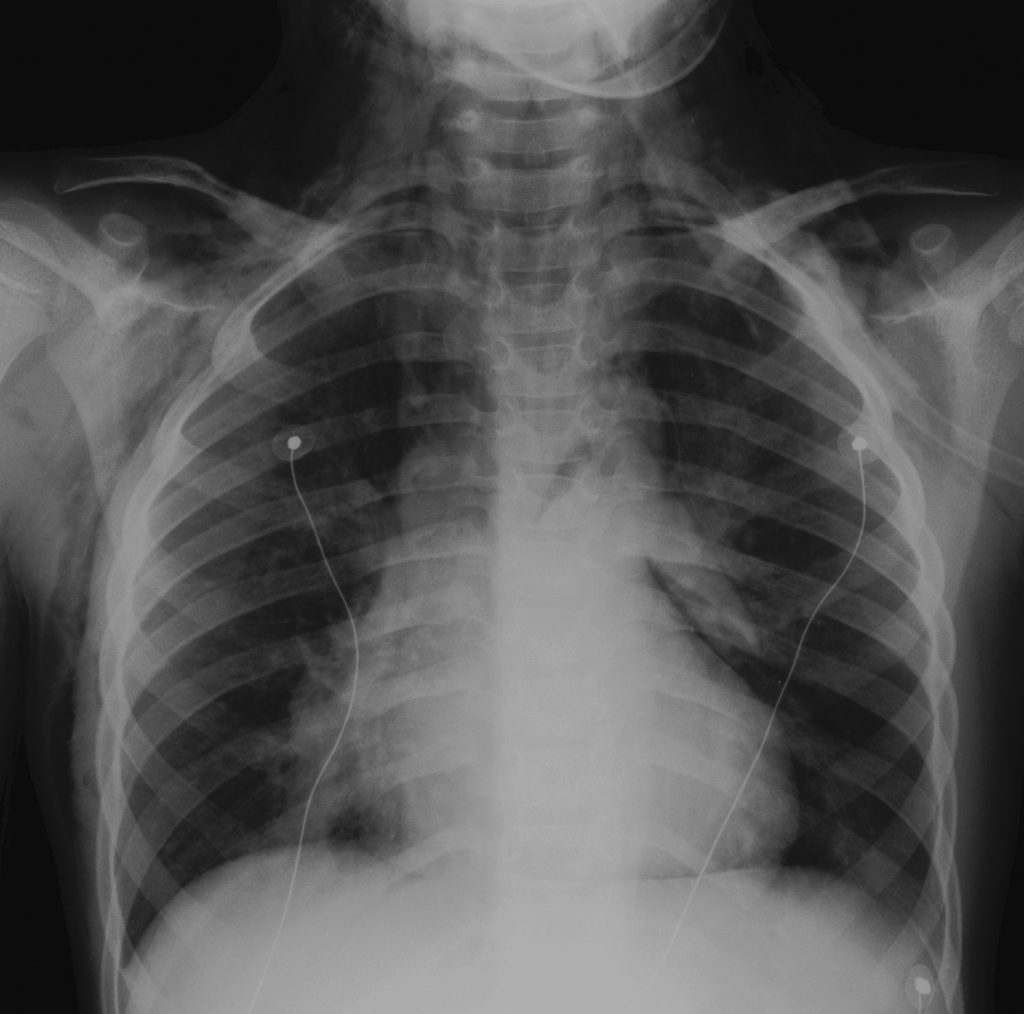

La radiographie thoracique retrouve classiquement une distension thoracique et un épaississement péribronchique. Des atélectasies sont possibles.

La distension thoracique se traduit par une hyperclarté des champs pulmonaires avec un aplatissement des coupoles diaphragmatiques et une horizontalisation des côtes. L’épaississement péribronchique se traduit par des images linéaires en rail ou en anneau.

Fig. 121.1 Asthme sévère : pneumomédiastin avec emphysème sous-cutané.

Source : CERF, CNEBMN, 2022.